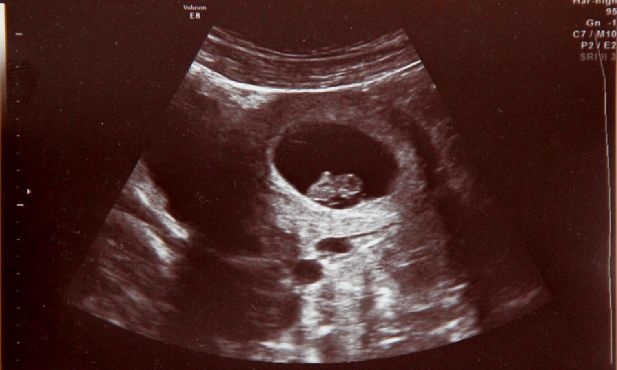

Do niedawna poważne wady płodu oznaczały dramat i brak nadziei. Postęp perinatologii sprawił, że lekarze diagnozują i leczą dzieci w łonie matki - powiedział prof. Przemysław Kosiński. Ale żeby leczyć, trzeba rozpoznać. Dlatego zaleca, by USG wykonywać co najmniej trzy razy w czasie ciąży.

- Kluczem jest jednak diagnostyka prenatalna. Bo żeby leczyć, trzeba najpierw rozpoznać. USG jest bezpieczne i powinno być wykonywane co najmniej trzy razy w każdej ciąży. Czasem jedno badanie decyduje o tym, czy dziecko będzie żyło - podsumował specjalista.